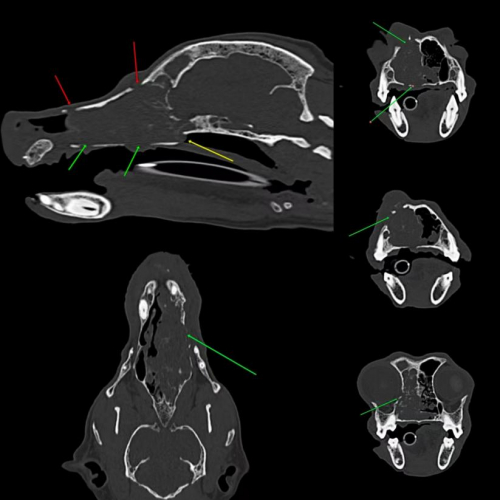

高清40排,宠物也能做CT

一般来说,探测器排数决定了CT的档次,联影这款CT则具备同类型最高档的40排探测器,并且同时满足了22 毫米的覆盖宽度和0.55 毫米的探测器厚度,因此扫描速度和图像分辨率都表现相当优异。无论是常见的犬、猫、兔子等“毛孩子”,还是乌龟、蜥蜴、仓鼠等异宠,甚至仅有5-10厘米的蟋蟀,40排CT均能极速高清成像。

芭芭拉主治医生、国家执业兽医师林祎介绍,在宠物急诊、耳鼻喉疾病、胸部疾病、复杂骨科或微小骨折骨裂的鉴别、泌尿系统问题、肿瘤、血管类疾病、脊椎等临床应用方面,40排CT皆可发挥极大效用。

林医生提到,有时候宠物从外观来看也许没有异样,但是通过uCT 528则能发现深层问题。她曾遇到一位鼻腔肿瘤患宠,主要症状是流鼻血打喷嚏,整体外观看起来并无明显变化,似乎并不严重。出于慎重,林医生为其做了一个CT鼻腔扫描,从图像却能明显看见很大的肿瘤,并且已经侵袭到鼻中隔和上颚骨,方才准确查明病因,尽早制定了更加合适的诊疗方案。